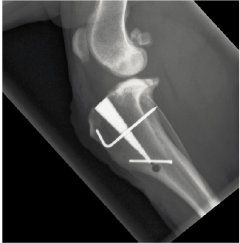

MMP ACL/CCL

The MMP CCL surgery redirects the force generated by the large quadriceps muscles to the patellar tendon to compensate for the failed cruciate ligament. This is achieved by moving forward the part of the tibia (the tibial tuberosity) attached to the quadriceps muscle. The patella tendon then acts in the same way that the previous CCL ligament did to stabilize the knee.